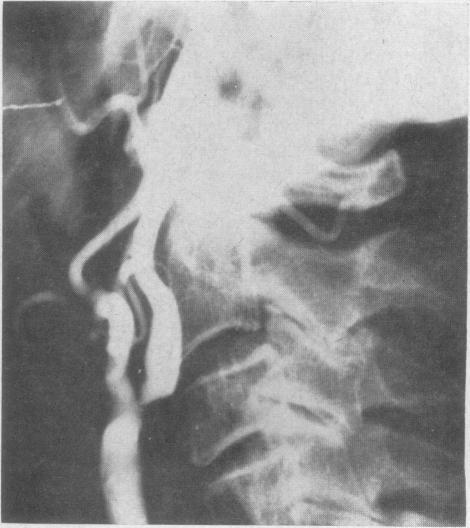

A method of providing adequate cerebral blood flow during carotid artery thromboendarterectomy.

Can Med Assoc J. 1962 May 5;86(18):835-7.